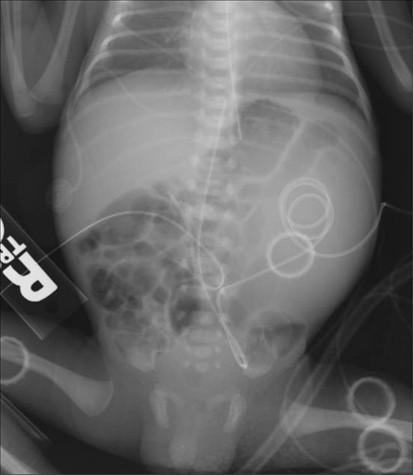

Mesoblastic Nephroma Radiology Google Search Radiology Renal Peds